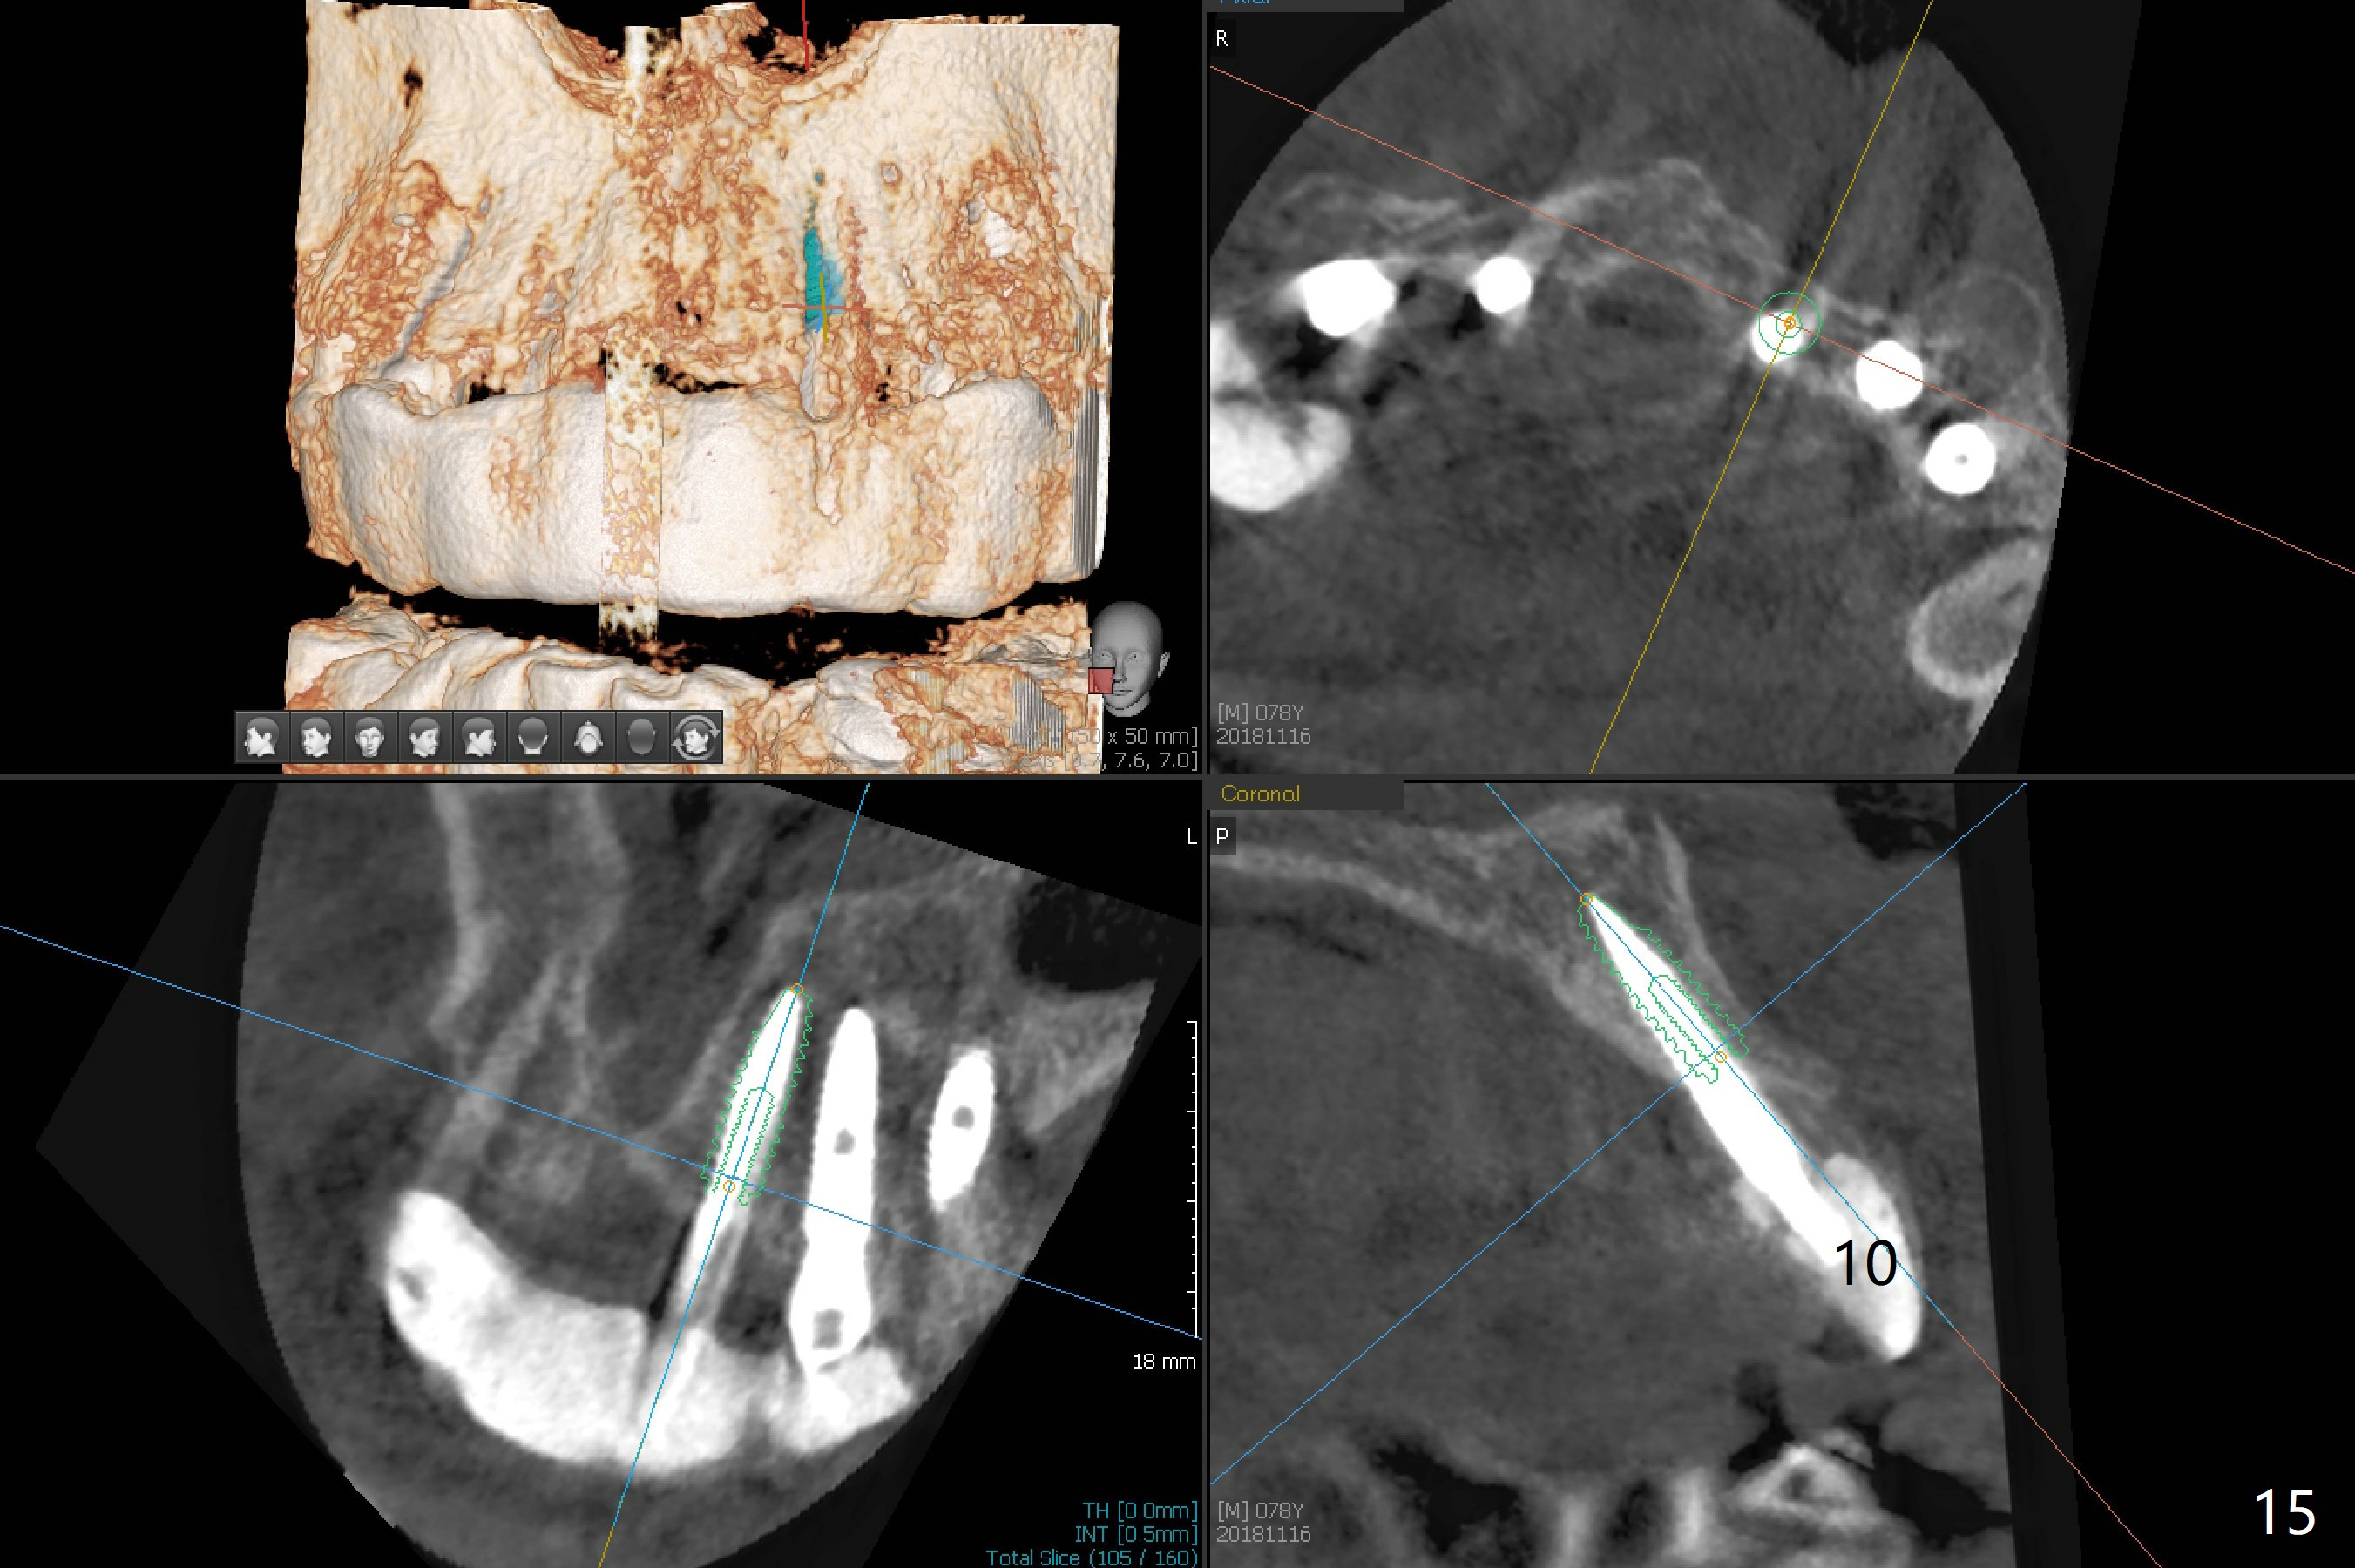

It is smooth and quick to finish osteotomy with guide at #6,7,10-12, but when 3 mm 1-piece implants are placed free hand at #7 and 10 (Fig.1,2), the gingival parts of the abutments contact the incisal edges of the lower incisors (anterior deep bite) in spite of effort to change the trajectory by repeated back and forth placement after use of Lindamann bur buccally. Following an immediate provisional (Fig.3,4), the occlusal surface of the posterior teeth are raised to eliminate anterior restoration interference. Immediate postop CBCT shows that the implants at #7 and 10 could be placed more buccally (Fig.6,7, as compared to the normal position at #6,11,12 (Fig.5,8,9)). Fig.10 was taken 2 days preop, while Fig.11-13 postop. Can we change 1-piece implants (3mm) at #7 and 10 to 2-piece one (3.5) and use angled or cementation abutments for easy restoration (Fig.14-16)?